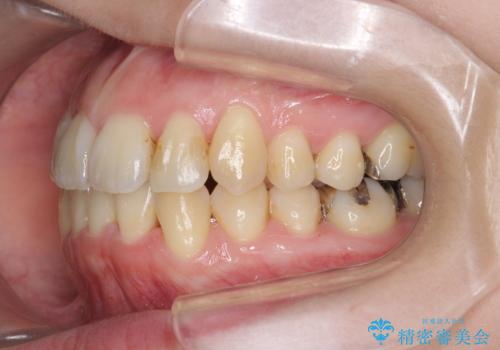

前歯のがたつき すれ違い咬合のマウスピース矯正治療

- 前歯のがたつきや歯の角度、矯正治療を希望され来院されました。

仕事の都合で、ワイヤー矯正を行うことが難しくマウスピース矯正であれば可能、という希望でした。

下顎が前にある咬合関係を可及的に咬合移動で改善し、IPR、下顎3前歯の仕上げで行うマウスピース矯正を計画します。

他院では、「マウスピース矯正では治らない。」と言われ当院に相談に見えましたが、マウスピースで達成できるゴールを模索することで矯正治療を行えることがあります。